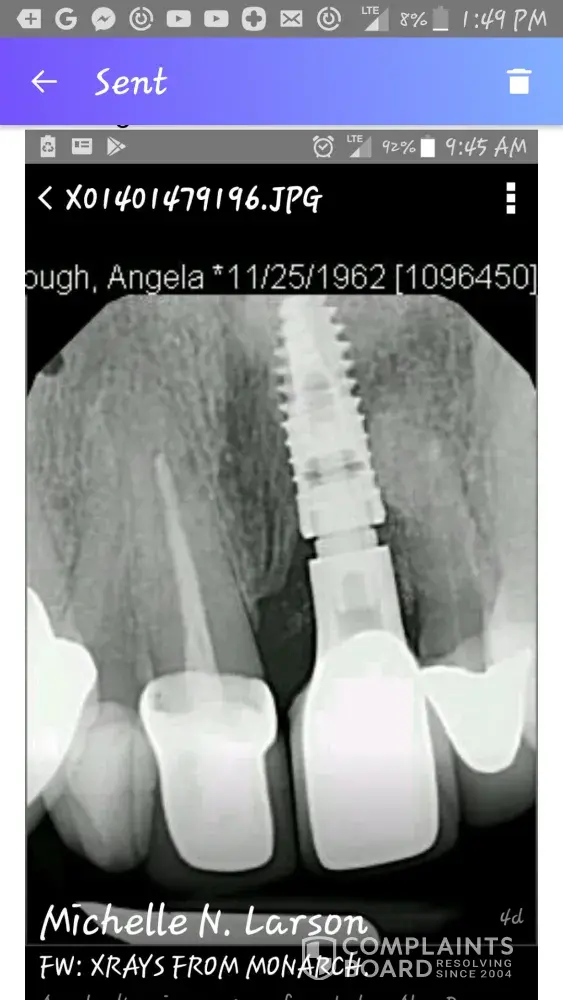

For the THIRD TIME I had an implant crown replaced in my front tooth and STILL WAS NOT DONE correctly! I sent a letter to the Regional Manager about 2 months ago requesting reimbursement and still haven't heard from anybody! I'm NOT happy with my smile and I need the money back so I can go to another dentist to fix and improve my smile!